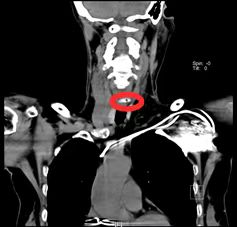

先来看看两个真实案例:张阿姨(化姓)早上喝红枣小米粥时,边喝边和家人聊天,不小心把一颗枣核吞了下去。当时她感觉喉咙下方有点梗阻,吞咽时还有疼痛感,但想着喝点稀饭也许能把枣核冲下去,结果胸口疼痛越来越剧烈,赶紧去了中大医院,找到耳鼻咽喉头颈外科冯旭主任医师。医生在食管镜下发现,枣核尖锐的两端已经深深扎进了食管壁。另一位梁大爷(化姓)早餐喝八宝粥时,也误吞了里面的枣核,立刻出现吞咽剧痛、无法进食的情况,找到中大医院耳鼻咽喉头颈外科朱新副主任医师。CT 检查显示枣核横插在食管内,经过紧急手术,异物成功被取出。